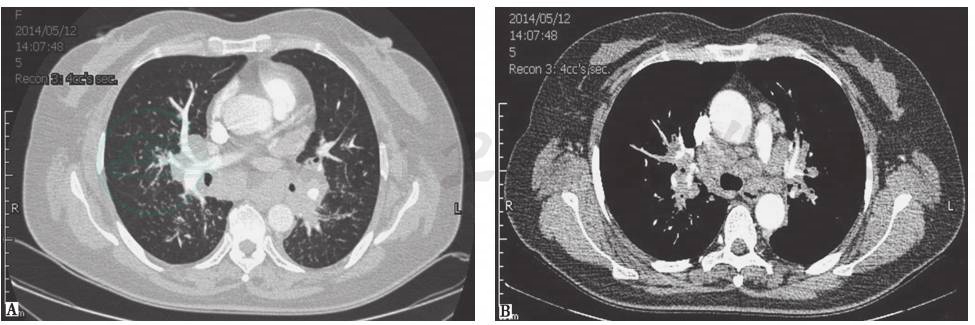

胸部CT:纵隔内见多组淋巴结肿大,斜裂胸膜区多发小结节影,双肺间质纹理增多,双侧胸腔积液,少量心包积液(图1)。

图1 胸部CT表现

胸部CT可见纵隔多组淋巴结肿大,双肺间质纹理增多,双侧胸腔积液,右侧胸腔积液更为明显